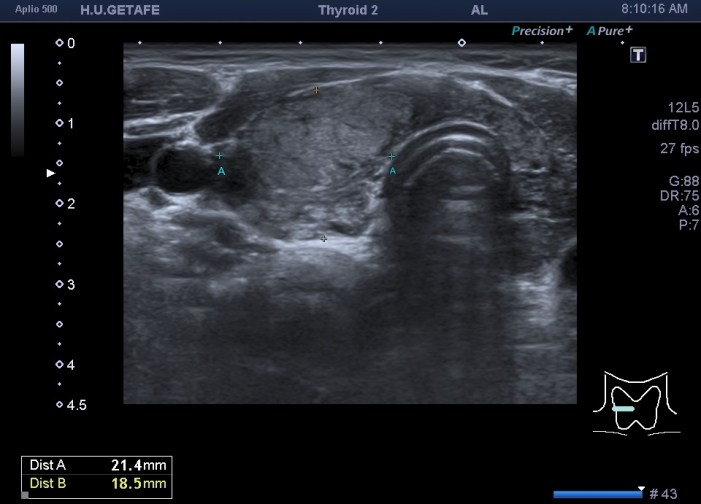

De la imagen 1 a 7 el protocolo habitual, el estudio particular del nódulo con medidas y aplicación del doppler demuestra el aspecto típico del Caballero Blanco.